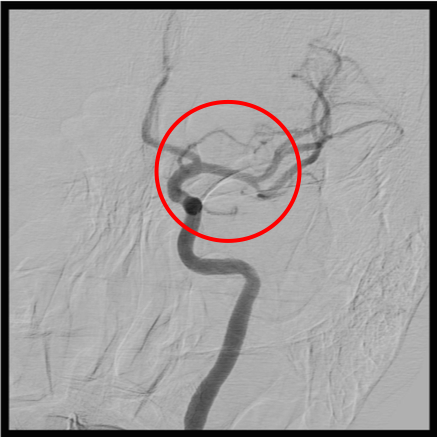

前交通動脈瘤

術前の造影写真です。〇内に脳動脈瘤が造影されています。

動脈瘤内にマイクロカテーテルを挿入しステントを展開しています。

術後の造影写真です。主幹動脈は温存できており、動脈瘤は造影されなくなっています。